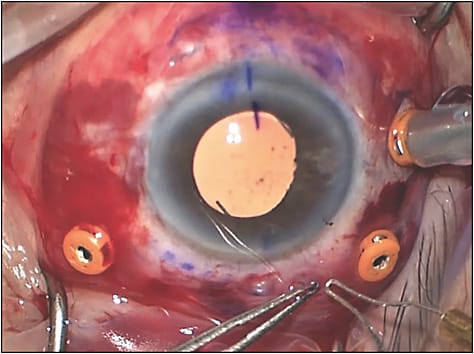

Positioning of the externalization cannula is critical to avoid IOL tilt and decentration. Start by using a corneal marker centered on a dry cornea using the limbus — not the pupil — as a base (Figure 1A). I externalize at 1 o’clock and 7 o’clock in right eyes and at 11 o’clock and 5 o’clock in left eyes, accounting for the nasal bridge. Make your marks exactly 180° apart and then mark 2 mm to 2.5 mm posteriorly to the limbus, avoiding areas of conjunctival fibrosis, blebs, or tube shunts. When placing the externalization cannulas, bevel at 30° to 45° following an inverted “S” and then enter the vitreous cavity perpendicularly to the ocular surface to complete the biplanar scleral tunnel. It is critical that the bevel angle, tunnel length, and point of entry be exactly mirrored on the other side. Symmetrical “puckering” of the cannulas often indicates good placement (Figure 1B). After these cannulas are placed, the other ports can be inserted in usual fashion. For left eyes, place the infusion line inferonasally to keep it out of the way.

If rescuing an IOL, you can also mobilize it to the anterior chamber and follow the steps above. However, it is often easier to keep the IOL in the posterior segment. Simply insert retina forceps through either the superior or inferior cannula, grab the haptic tip, and follow the same aforementioned externalization process (Figure 4A). Then, use the retina forceps through the contralateral cannula, grab the haptic tip, and again externalize (Figure 4B and 4C). This method works best utilizing the indirect visualization system, so you will need to flip it in and out as you move between grabbing the haptic and externalizing it where direct visualization is necessary. Some have used chandelier endoillumination to facilitate a bimanual approach, but I have not found this necessary.

- When grasping the haptic tip, elevate it slightly upwards off the wet ocular surface. Soak up surrounding fluid with a Weck-Cel sponge (BVI) to help the haptic form as desired (Figure 5A and 5B).

- Minor centration adjustments can be made while forming the flanges (Figure 6). Adjust the haptics to see how the IOL optic is best centered; trimming one haptic before flanging it can sometimes be beneficial, but do not shorten it so much that the haptic is on tension.

Once the flanges have been created, use tying forceps to gently nudge them until they reside just beneath the external opening of the scleral tunnel (Figure 5C). If insufficiently buried, the patient may experience a foreign body sensation, or worse, the haptics may erode through the conjunctiva. Opening the conjunctiva in this procedure is generally not necessary, but do not hesitate to create a small localized peritomy if needed for visualization. As with all my combined cases, I like to suture the 3 vitrectomy port sclerotomies to prevent hypotony. Lastly, I will mention that some place a prophylactic peripheral iridotomy to prevent reverse pupillary block, which has been reported postoperatively.9,10